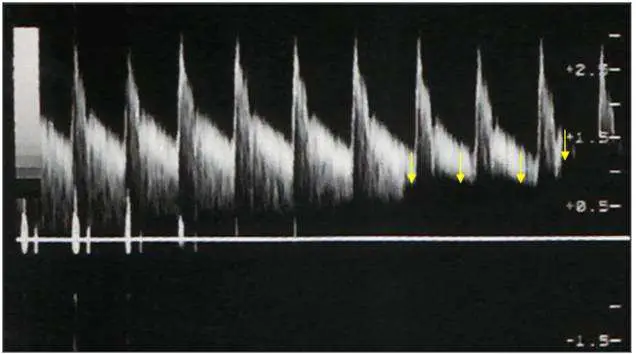

本圖為頸動脈(carotid artery)的都卜勒頻譜圖(spectral Doppler waveform),速度縱軸約為 -1.5 到 +2.5 m/s。

- 波形輪廓呈高尖峰型(tall, sharply peaked systolic waveform),每個心跳循環均見

- 三枚黃色箭號指向波形之間及頻譜基線附近的區域——頻譜窗口(spectral window)內部呈現亮白填滿現象,原本應為清晰暗黑的窗口不再存在

- 基線附近的低速訊號(low-velocity signals)明顯缺失或被截斷,波形底部與基線之間有不正常的訊號空缺